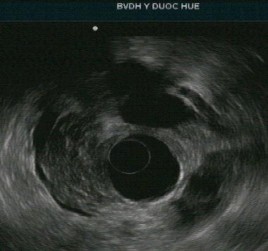

Tổn thương ống tụy: sỏi ống tụy chính, giãn ống tụy, thành của ống tụy chính không đều, tăng âm thành ống tụy chính. Nhu mô tụy thấy các nốt và dải tăng âm. Chẩn đoán chắc chắn viêm tụy mạn với tiêu chí chính A và bốn tiêu chí phụ.

Tổn thương ống tụy: ống tụy chính không giãn nhưng có tăng âm thành ống tụy. Nhu mô tụy: tổn thương dạng tổ ong, các nốt tăng âm không có bóng lưng kèm các tổn thương trống âm. Chẩn đoán nghi ngờ viêm tụy mạn với 1 tiêu chí chính B kèm 3 tiêu chí phụ.